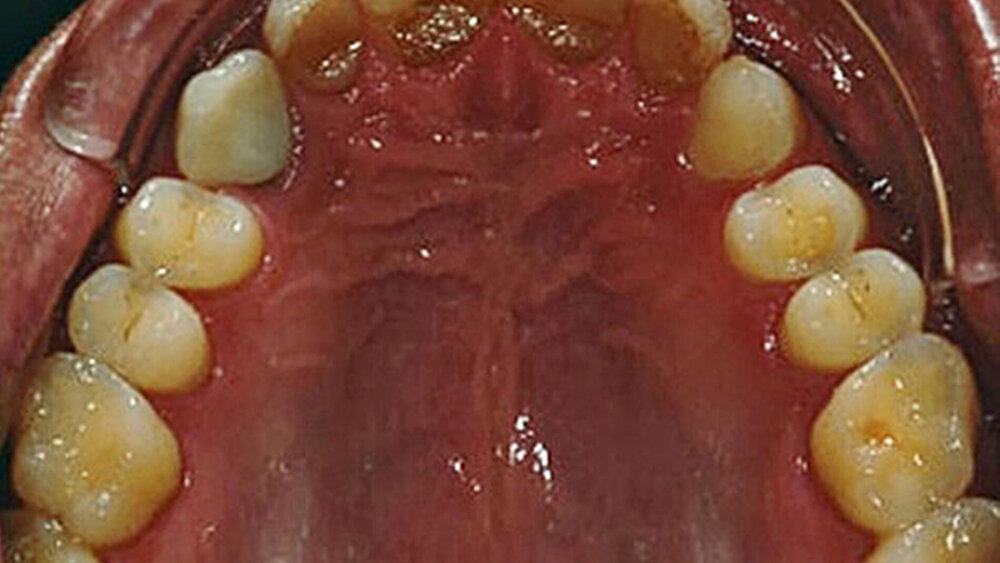

2015 stellte sich ein 47 Jahre alter Mann mit Schmerzen im TMG (Temporomandibulargelenk) vor. Er hatte außerdem ein ästhetisches Anliegen, da ein Stück vom Veneer eines mittleren oberen Schneidezahns abgebrochen war (Abb. 1–3). Die klinische und radiografische Analyse (Abb. 4) ergab einen Verlust der Bisshöhe und der Zahnsubstanz aufgrund von Bruxismus.

Digitale intraorale Fotos wurden aus der Vorderansicht unter Retraktion sowie aus der Okklusions- und lateralen Ansicht erstellt. Zudem wurden mit einer digitalen Spiegelreflexkamera (DSLR) zusätzliche Fotos erstellt (frontal, lateral und 45º). Eine diagnostische Abformung beider Kiefer wurde mit einem intraoralen Scanner (Carestream 3500) durchgeführt. Die maximale Interkuspidationsposition (MIP) wurde intraoral mit dem intraoralen Scanner Carestream 3500 erfasst, und die neue Vertikaldimension der Okklusion (VDO) wurde durch entsprechend weites Öffnen des virtuellen Artikulators in der CAD/CAM-Software (CAD/CAM = computergestützte Konstruktion und Fertigung) erreicht.